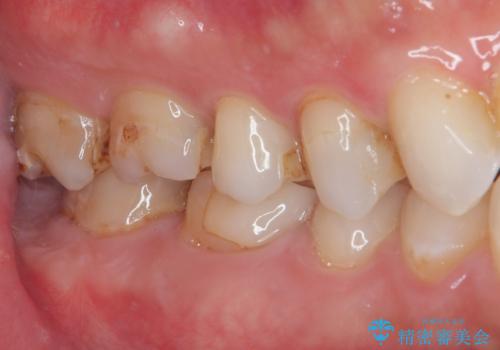

- セラミックの詰め物が欠けたのでやり替えたいとのことで来院された患者様です。

右下の6番目の歯は初診時から詰め物が大きかったため、被せものでの治療を提案していましたが、患者様の強いご希望でセラミックの詰め物(セラミックインレー)での治療をされていました。今回メインテナンス時に来院されたときに被せもの(オールセラミッククラウン)での治療を再度提案させていただき、患者様にも納得をしていただいたうえで、オールセラミッククラウンによる治療を行いました。

拡大鏡視野下で、セラミックの詰め物(セラミックインレー)、虫歯の除去を行い、オールセラミッククラウンに適した形に整えました。